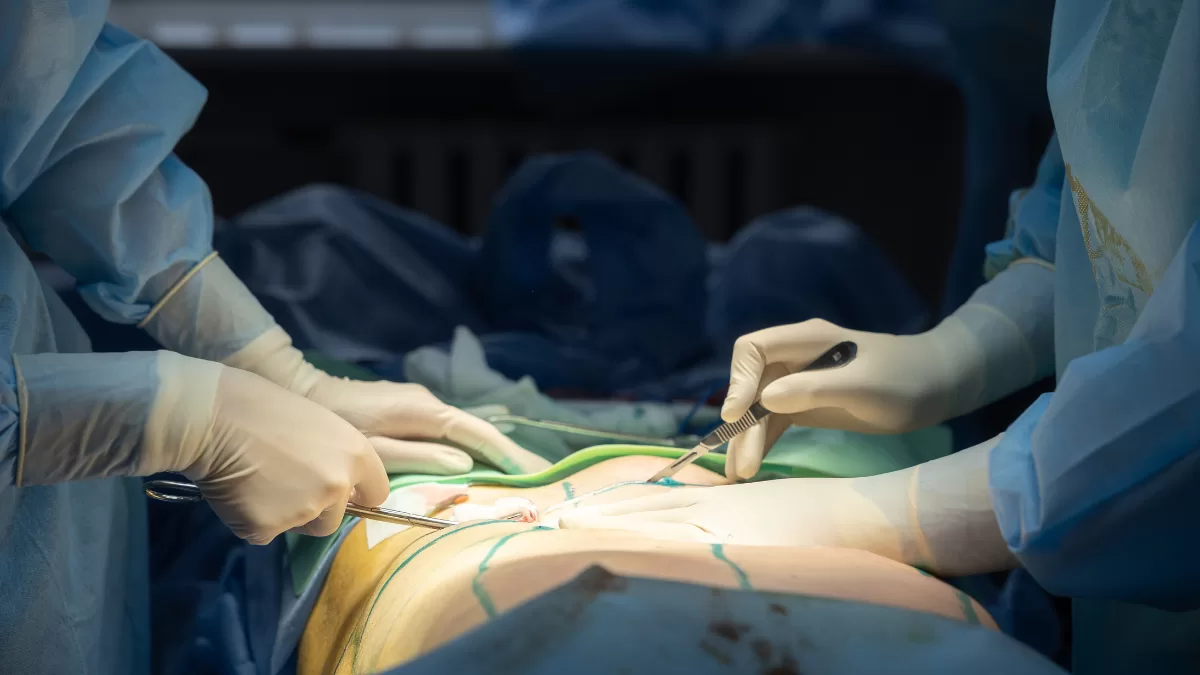

Por otro lado, Kathy Contreras anunció que se lesionó practicando para su última presentación.

“En el ensayo de este último baile me lesioné la costilla derecha. (No me di cuenta por la adrenalina, pensé que era una contractura y por eso baile igual. Y al otro día seguí ensayando, hasta que me hicieron una radiografía). Ahora estoy con algunos días de reposo, pero volvemos luego. Los que me conocen saben que pienso con respecto a los síntomas del cuerpo, bendito síntoma que viene a mostrarme cosas”, reveló Kathy Contreras.